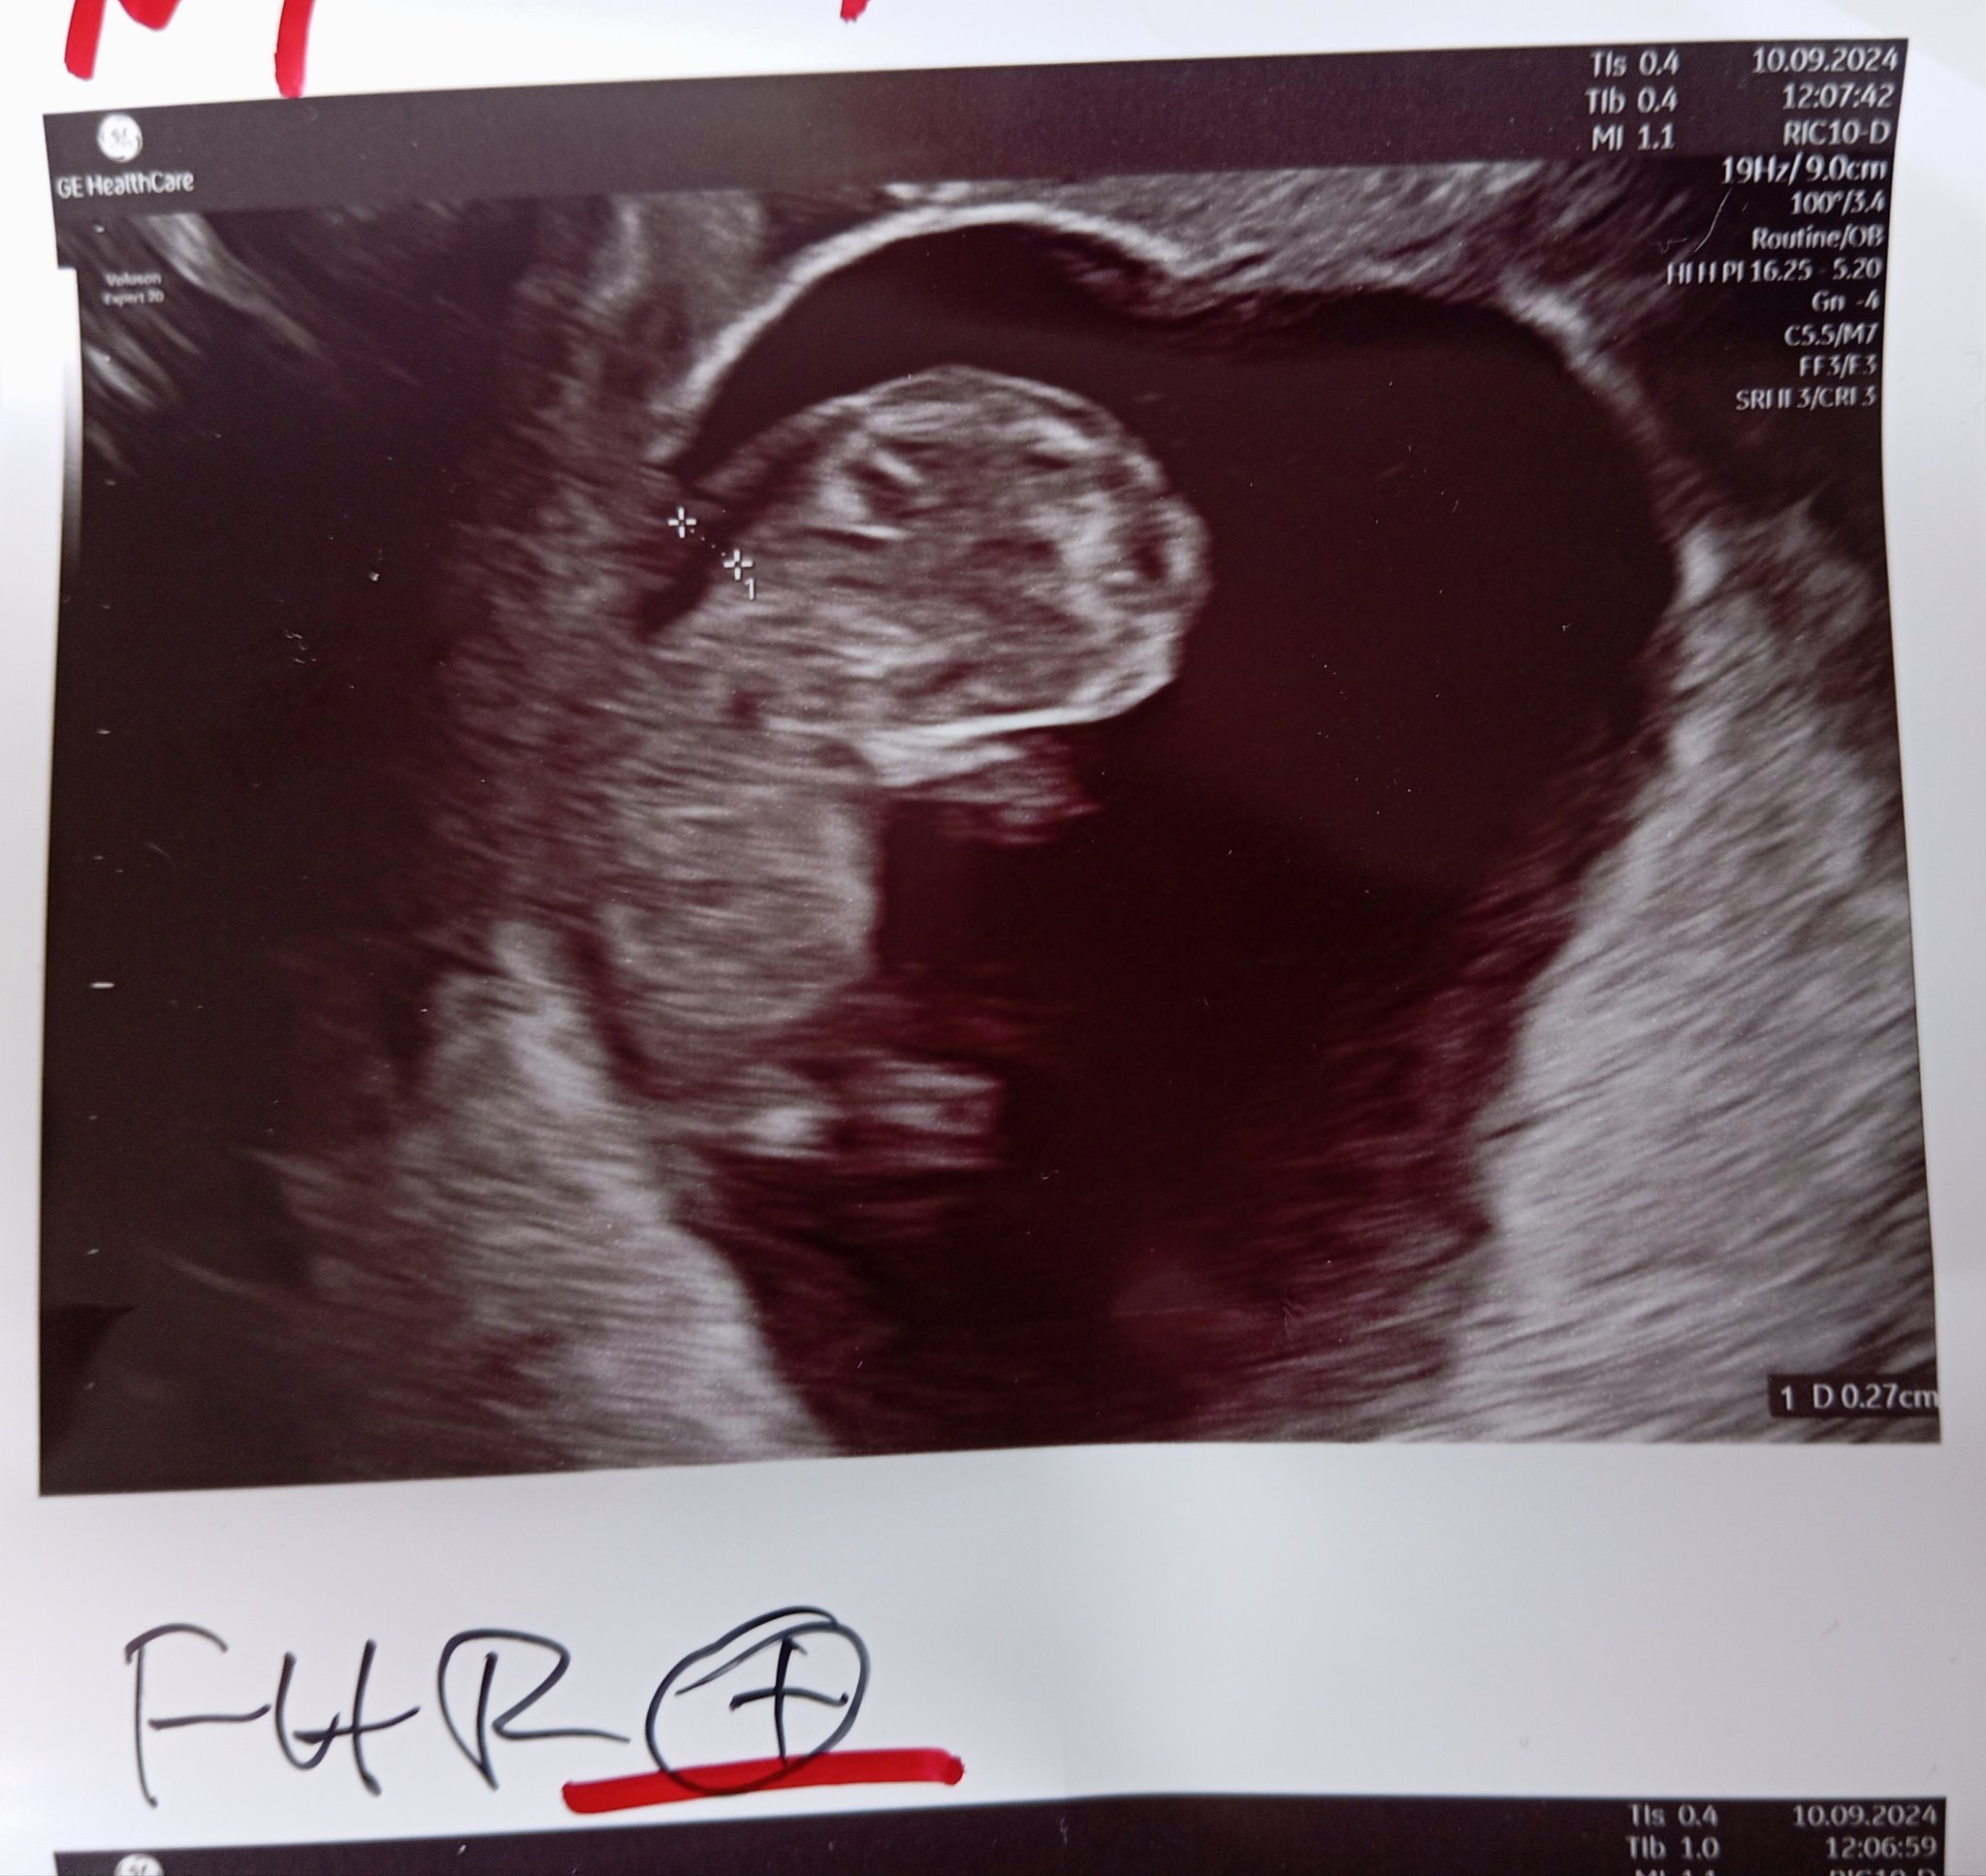

Какво представлява NT и какви са нормалните стойности?

NT (neck thickness или гъвкавост на врата) е ултразвуков показател, който се измерва за оценка на риска от хромозомни аномалии. Нормалните стойности за NT са под 3 мм, но за точна интерпретация е необходимо да се разглеждат и други маркери. Стойности над 3,5 мм увеличават риска и могат да наложат допълнителни изследвания.